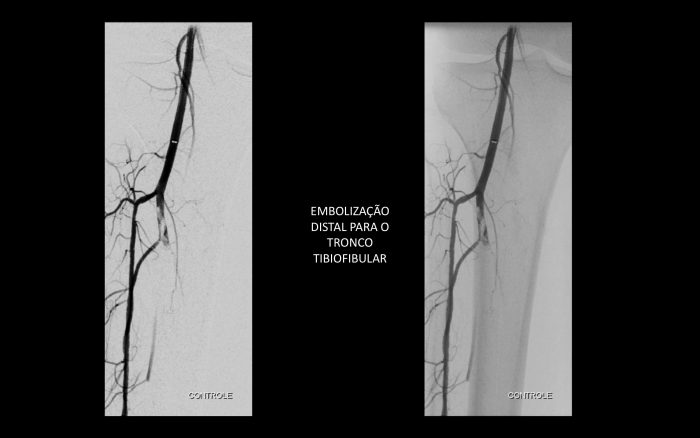

Paciente com história de claudicação dos membros inferiores para curtas distâncias, já submetido a angioplastia do membro inferior direito, retorna ao serviço com piora dos sintomas no lado esquerdo, sem lesão trófica (Rutherford 3)